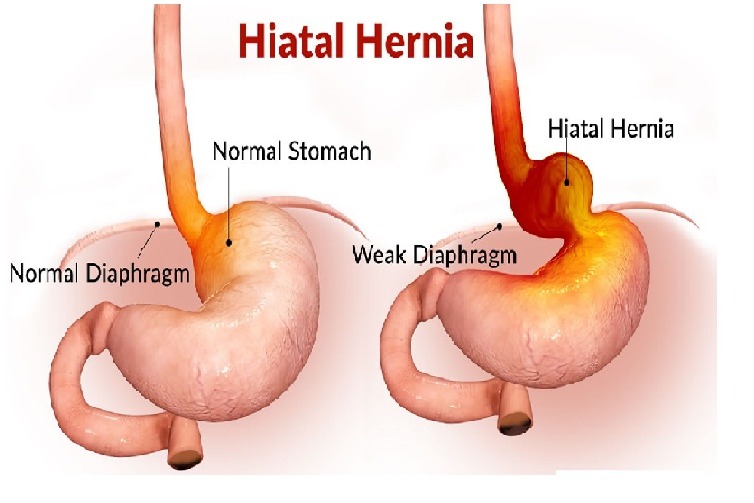

Back in January 2004 I was diagnosed with a large Hiatal Hernia with extreme GERD I then had a laparoscopic Nissen Fundoplication to try and repair this. After the surgery I still felt the sliding up and down motion and found it hard to breathe. I then went back to the surgeon that repaired it and he said it was fixed. I knew It wasn’t right, so I went and searched for other doctors. I found a doctor out of state and he also said I did not have a Hiatal Hernia. I told him I had “A knocking below my sternum” and so he removed half of it this left a Ventral and Incisional Hernia and I still felt an up and down motion leaving me extremely short of breath. I then found another G.I. doctor who found the problem. I had a large Sliding Hiatal Hernia at the 35cm at the E.G. Junction with the Nissen intact. He referred me to a surgeon who confirmed a Ventra Hernia with many adhesions. He never repaired the Hiatal Hernia, but the mesh and adhesion removal helped, and I’ve been functional for 14 years. However, I started working at a wholesale club where I had to twist and bend while lifting heavy things. At the same time, I contracted Bronchitis and I coughed a lot and gagged. I felt something pop and then all my symptoms began. I was able to get a surgeon right a way who did a CAT Scan. The CAT Scan showed a large Ventral and Abdominal Wall Hernia. My stomach, liver, and intestines were protruding outside my Ventral and abdominal wall. The next day they performed emergency surgery. I had my original paperwork from 2004 but they refused to see it. They opened me up and put mesh in the Ventral and Abdominal Wall. This seem to only make my breathing and sliding of my Hiatal Hernia worse. They said I did not have/ did not see a Hiatal Hernia. This seems impossible because they don’t just magically disappear. A week and a half post-surgery every time I breathe or talk it feels like my stomach is moving up and down and slamming into the mesh they placed in the Ventral area. I am unable to eat, sleep, or breath very well. I do not have any quality of life because I am too out of breath and this big bulge comes up when I breathe. I have told them of my symptoms, but the surgeon says he will not do anything until the surgery heals. I feel helpless and feel with every breathe I am going to die. I can’t eat so I am very weak. I need help fast and I don’t know what to do.

Back in January 2004 I was diagnosed with a large Hiatal Hernia with extreme GERD I then had a laparoscopic Nissen Fundoplication to try and repair this. After the surgery I still felt the sliding up and down motion and found it hard to breathe. I then went back to the surgeon that repaired it and he said it was fixed. I knew It wasn’t right, so I went and searched for other doctors. I found a doctor out of state and he also said I did not have a Hiatal Hernia. I told him I had “A knocking below my sternum” and so he removed half of it this left a Ventral and Incisional Hernia and I still felt an up and down motion leaving me extremely short of breath. I then found another G.I. doctor who found the problem. I had a large Sliding Hiatal Hernia at the 35cm at the E.G. Junction with the Nissen intact. He referred me to a surgeon who confirmed a Ventra Hernia with many adhesions. He never repaired the Hiatal Hernia, but the mesh and adhesion removal helped, and I’ve been functional for 14 years. However, I started working at a wholesale club where I had to twist and bend while lifting heavy things. At the same time, I contracted Bronchitis and I coughed a lot and gagged. I felt something pop and then all my symptoms began. I was able to get a surgeon right a way who did a CAT Scan. The CAT Scan showed a large Ventral and Abdominal Wall Hernia. My stomach, liver, and intestines were protruding outside my Ventral and abdominal wall. The next day they performed emergency surgery. I had my original paperwork from 2004 but they refused to see it. They opened me up and put mesh in the Ventral and Abdominal Wall. This seem to only make my breathing and sliding of my Hiatal Hernia worse. They said I did not have/ did not see a Hiatal Hernia. This seems impossible because they don’t just magically disappear. A week and a half post-surgery every time I breathe or talk it feels like my stomach is moving up and down and slamming into the mesh they placed in the Ventral area. I am unable to eat, sleep, or breath very well. I do not have any quality of life because I am too out of breath and this big bulge comes up when I breathe. I have told them of my symptoms, but the surgeon says he will not do anything until the surgery heals. I feel helpless and feel with every breathe I am going to die. I can’t eat so I am very weak. I need help fast and I don’t know what to do.